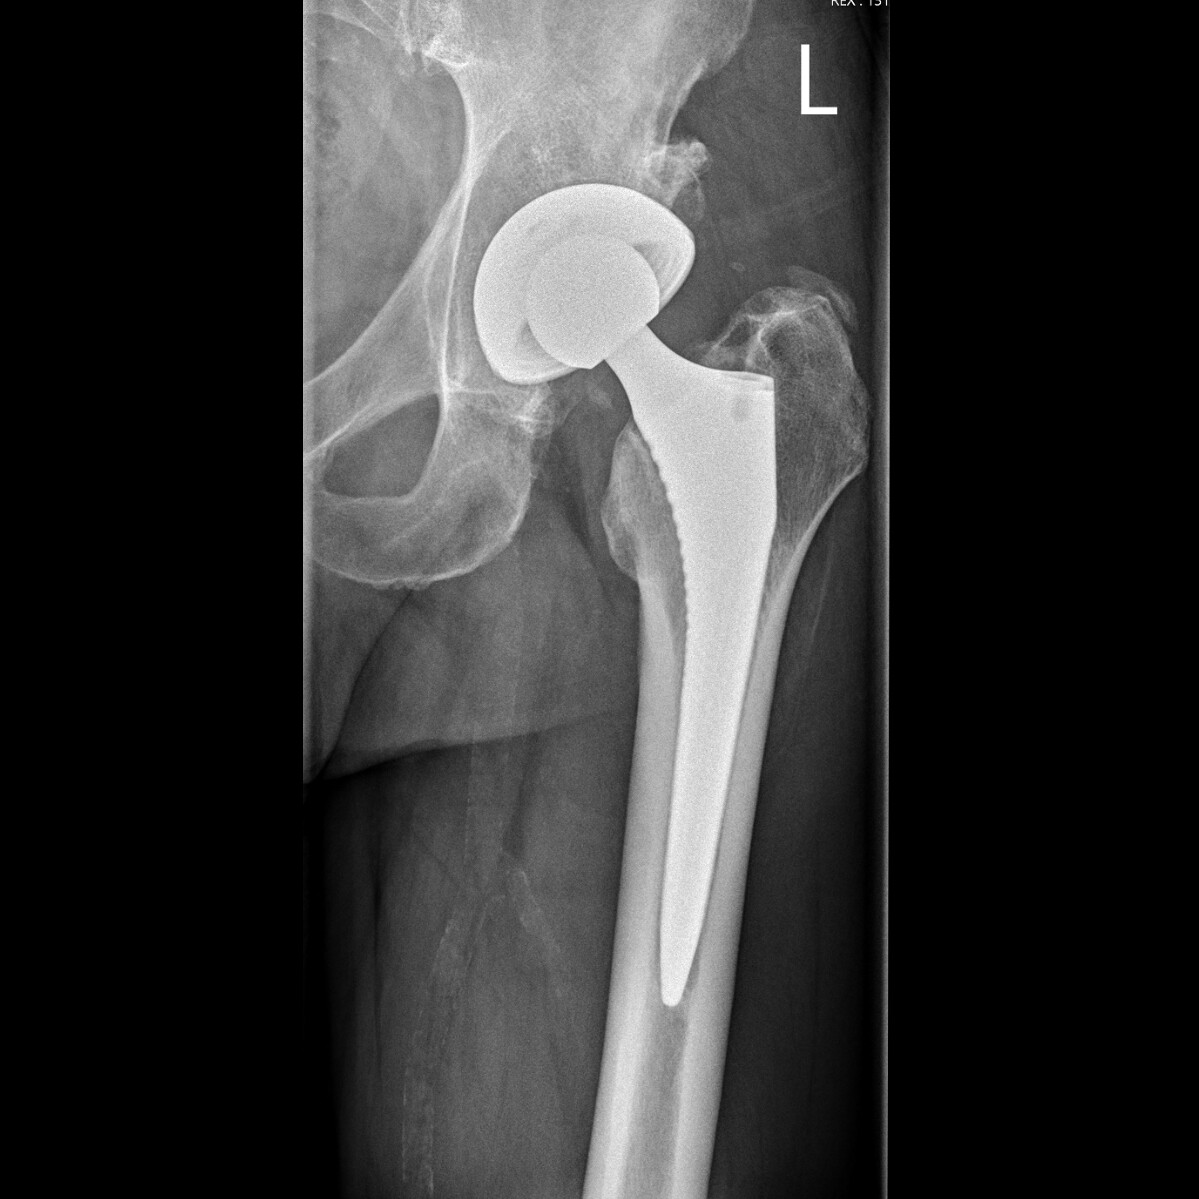

Hemi-arthroplasty (in this case a cemented stem with a bipolar head)